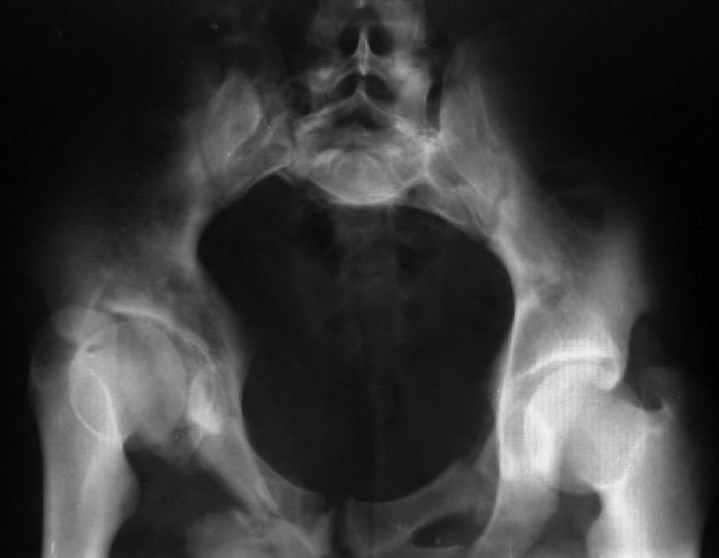

Для информации к размышлению о возможности исправления имеющейся деформации предлагаю похожий случай.

Уважаемый Юрий Алексеевич, обсудить показания к оперативному лечению возможно после выяснения полной клинической картины (боль, опороспособность, ходьба, сидение, половая функция, неврологический статус), данные кт и косых проекций.